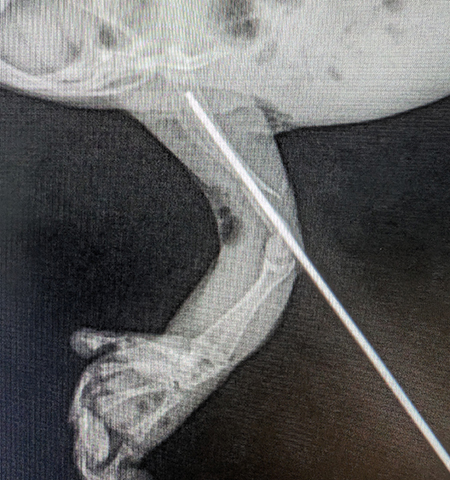

"Fig was brought in to us sporting a broken humerus, meaning her upper front arm was broken right in the middle, so it was in a perfect spot for us to put back together," said Breanna.

Fig’s recovery process was a unique one due to the tiny pin which was inserted into her arm as part of the surgery, which is rarely used as part of any procedure on wildlife.

"We went in through the outside of the bone, pushed it all the way through and that essentially helps to line the bone back up so it can heal in its natural position," said Breanna.